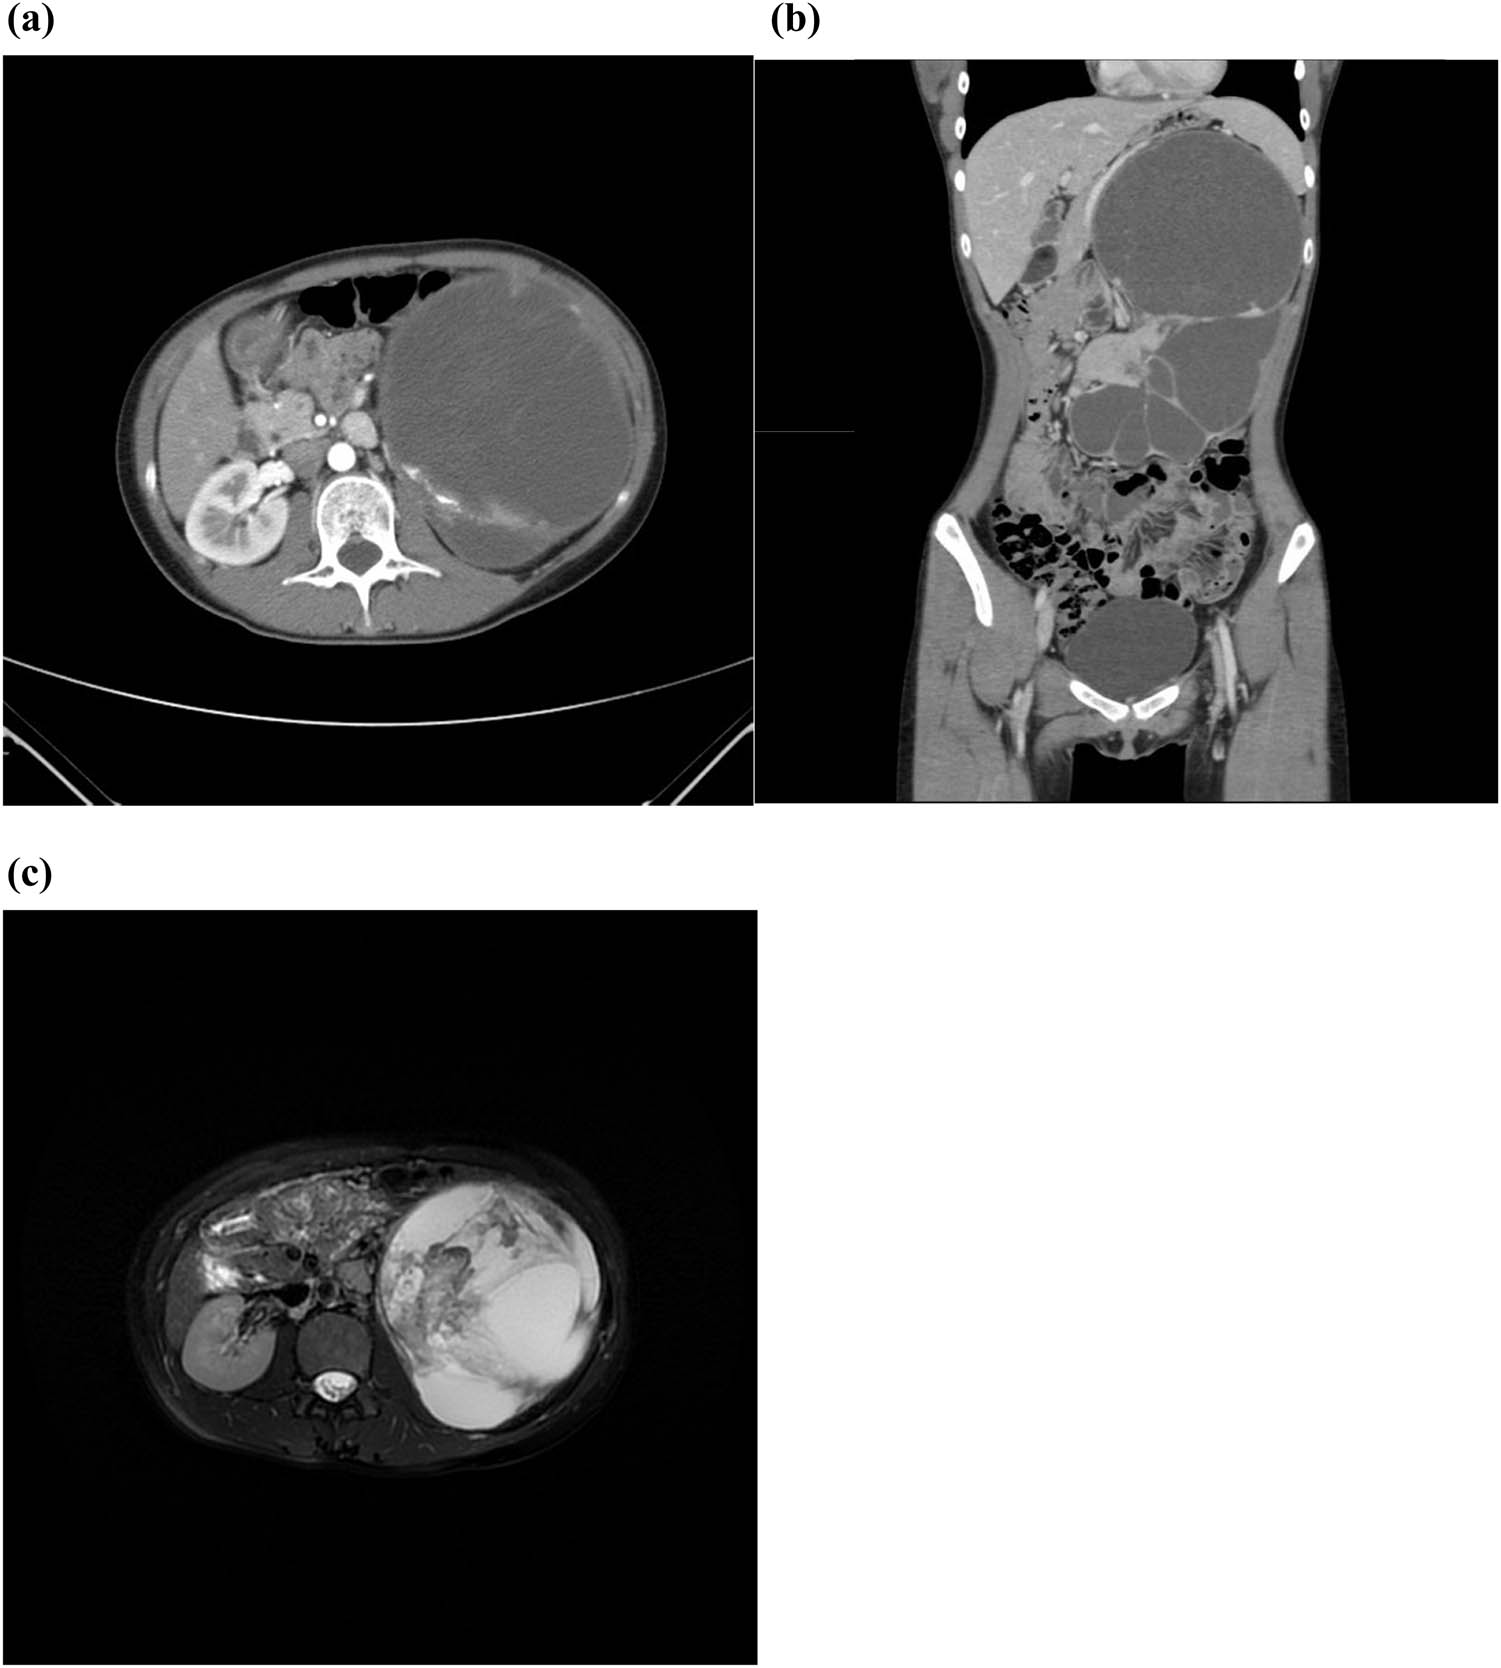

Four years later, on May 23, 2023, the patient, now 20 years old, revisited the Clinic of Urology with the complaint of a large mass in her left abdomen. Following admission to hospital, both eCT and enhanced MRI revealed the presence of left renal carcinoma with cystic changes, which had advanced considerably since March 30, 2019. The scans also detected invasion of the left calyces with left hydronephrosis. Furthermore, metastasis was indicated based on the observed enlargement of the retroperitoneal lymph nodes (Figure 4). The left renal glomerular filtration rate (GFR) was severely impaired, with GFR = 12.17 mL/min, while the right GFR was normal at 65.23 mL/min. No contraindications were identified during the preoperative evaluations. A palpable hard mass in the left upper abdomen was found during the physical examination.

A sizeable cystic kidney with increased compartments was detected in the left abdomen on eCT and MRI scanning in 2023: (a) transverse plane, (b) coronal plane, and (c) T2 scan.